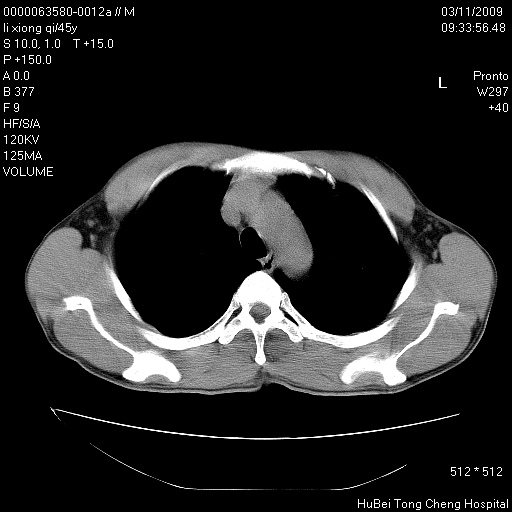

患者 男,45岁。胸痛,咳嗽伴痰中带血1月余。

临床诊断:肺结核?

胸部ct轴位平扫(层厚10mm,螺距1.5,重建间隔10mm),图像如下:

考虑肝癌肺转移

考虑肝癌肺转移。

肝癌肺转移